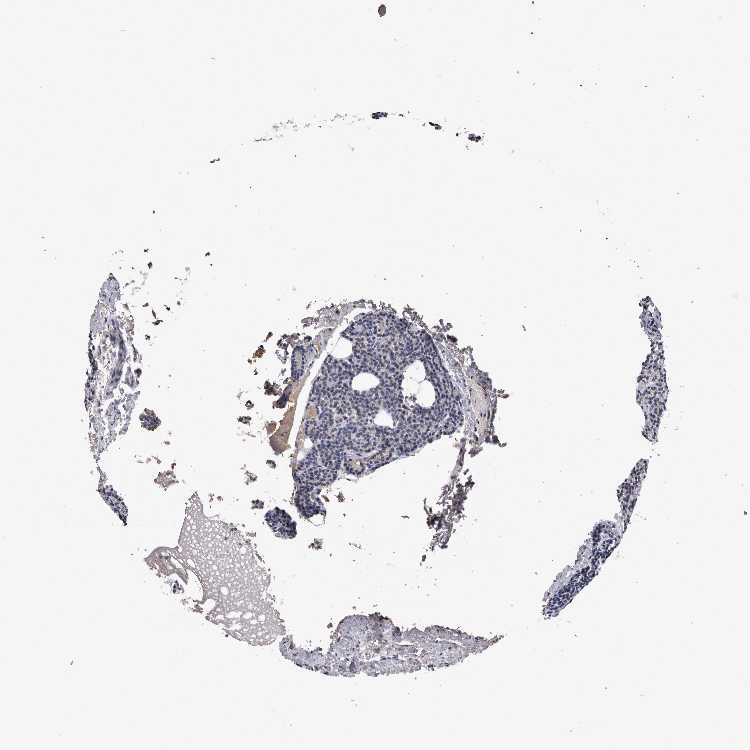

TISSUE PRIMARY DATA PARATHYROID GLAND Show tissue menu

PARATHYROID GLAND - Antibody stainingi

Antibody staining in the annotated cell types in the current human tissue is reported as not detected, low, medium, or high, based on conventional immunohistochemistry profiling in selected tissues. This score is based on the combination of the staining intensity and fraction of stained cells.

Each image is clickable and will lead to virtual microscopy that enables deeper exploration of all samples and also displays staining intensity scores, fraction scores and subcellular localization as well as patient and tissue information for each sample.

Antibody HPA015719Antibody CAB025894

Glandular cells Not detectedNot detected